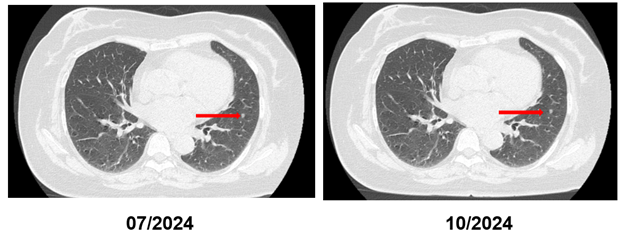

Đánh giá đáp ứng sau điều trị (10/2024):

CT ngực: Hìn ảnh hai nốt đặc 4–4,5 mm không thay đổi so với 07/2024.

Nhìn chung, hình ảnh học cho thấy đáp ứng rõ tại chỗ, và CEA giảm về bình thường; CA19-9 dao động và không song hành chặt với đáp ứng.